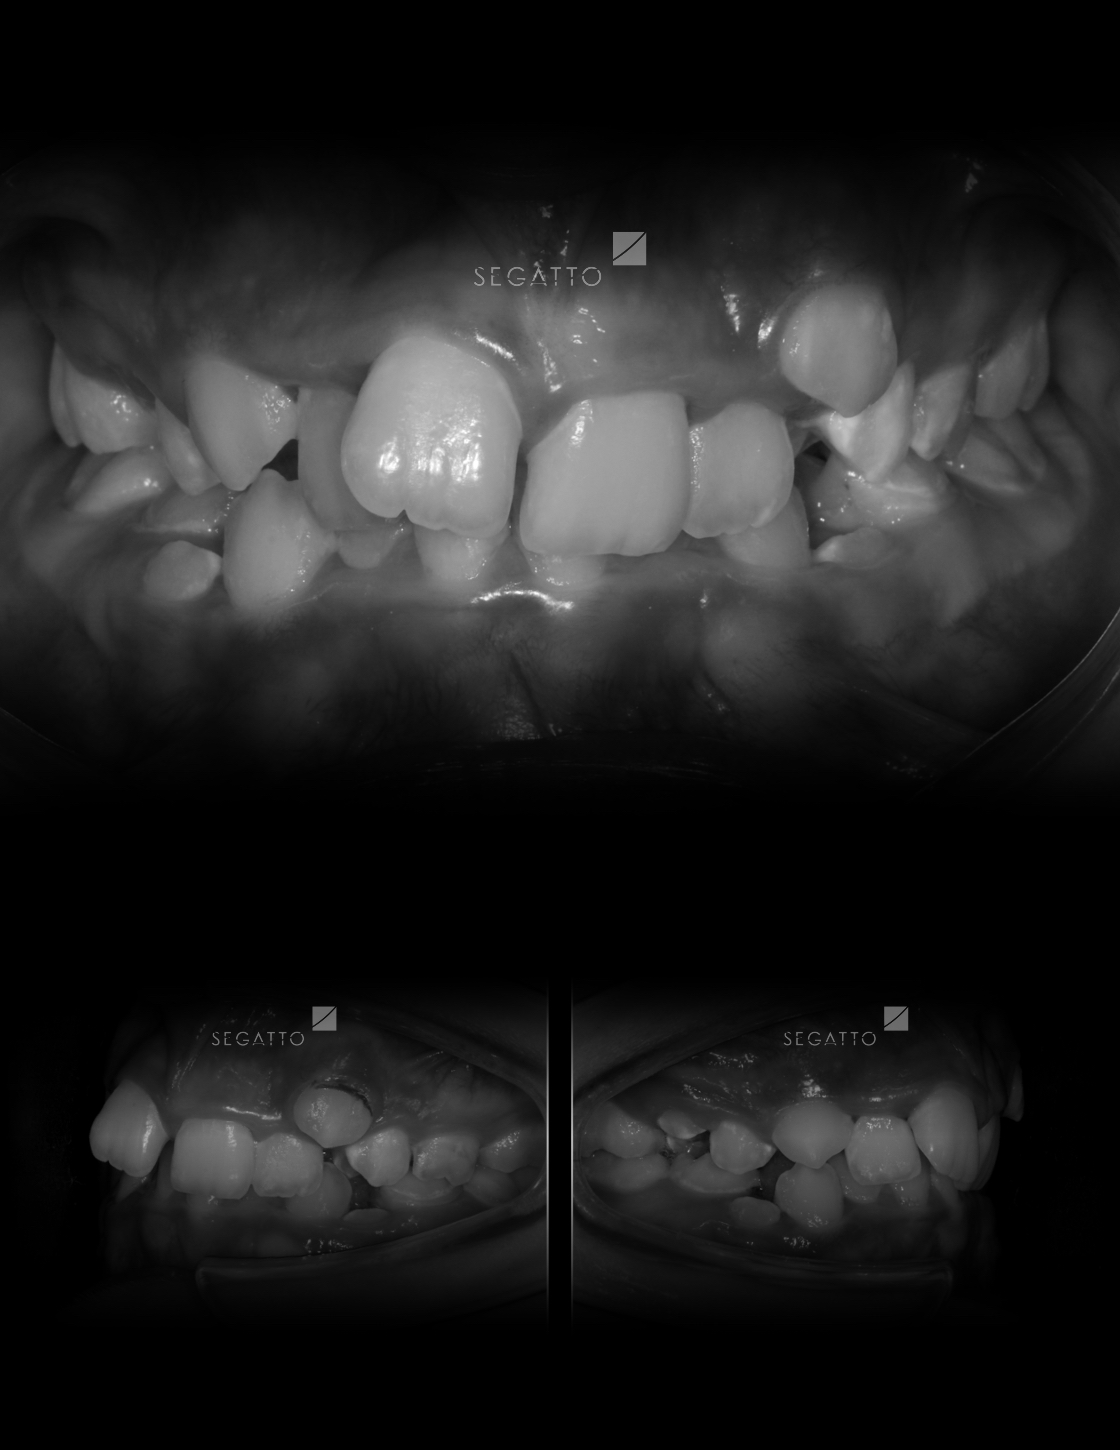

Orthodontics

Cases